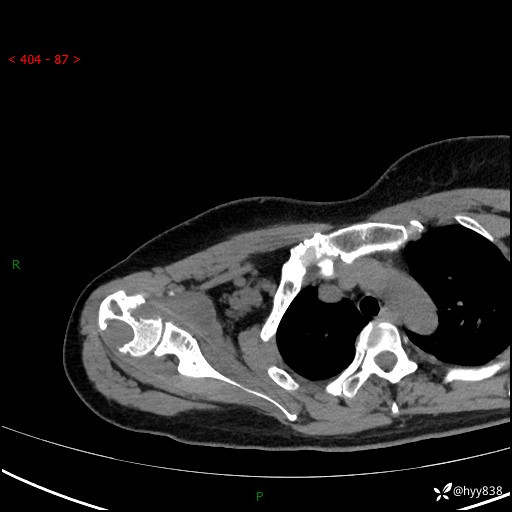

右肩关节CT平扫